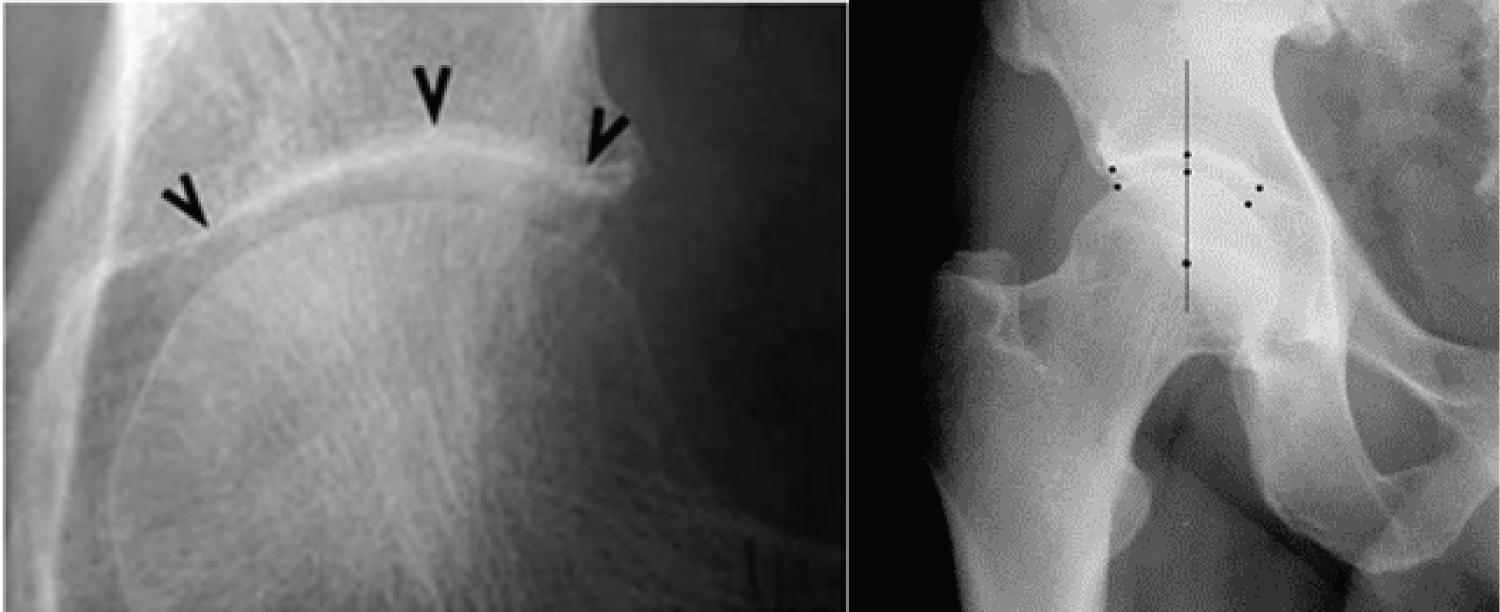

Radiographic examinations: The radiographic images were taken in an upright weight-bearing position, anterior-posterior projection, with a slight (15° degrees) internal rotation of the feet provided using a “V” pad -placed 100 cm from the source, with perpendicular beams focused on 4 cm above the symphysis. The following indicators were measured and evaluated: RGs according to К/L grading scale [65]; RPs-‘A’, ‘I’ and ‘H’; JSW - measurements of each joint were performed manually using distance measurement software for digitalised radiographic images at three points: Superomedial, apical and superolateral (Figure 2). The mean of the three distances (mean joint space width - mJSW in millimeters) and the annual velocity of joint space narrowing -JSN mm/yearly (JSN0 = mJSW-M0 - mJSW-M12) were used for the statistical analyses, according to the recommendations of the Barcelona Consensus Group [57].

Figure 2: Measurement of mJSW as the mean of the three distances according to the Barcelona Consensus (left image) [57] and in a patient from our study (right image). View Figure 2